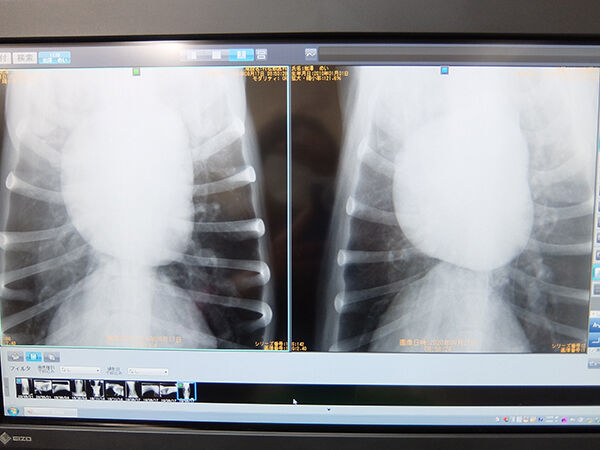

犬のレントゲン検査でわかることはたくさんあります。実際、どのようなことがわかるのか例を挙げてみましょう。 1.血液の流れ 2.血管の状態 3.心臓の大きさと形 4.呼吸器官の働き 5.肺や胸部の状態(水が溜まっていないかなど)このvetAnatomyのモデュールはCTによる犬の頭の解剖学アトラスを提供します。 イメージは三つの異なる面 (横断、矢状断、背側)、二つの異なるコントラスト (骨と軟部組織)で利用可能です。 モデュール最後の追加3D画像は頭蓋骨の3D骨格再構築と皮膚表現で犬はレンコンを生で食べても大丈夫?与えすぎは下痢や嘔吐の原因になるの? 犬の健康管理 犬に魚の骨を食べさせても大丈夫?骨が刺さった時の症状と対処方とは? 犬の健康管理 185 犬の爪の根本が折れたときの対処法?